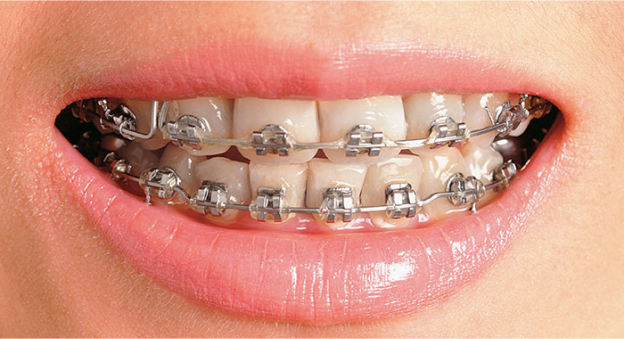

• 치열 불균형

전체적으로 치열이 변하면서 교정치료가 필요 할 수 있습니다.

보철치료는 심미성만을 위해 필요한 것이 아닙니다. 시간이 지남에 따라 인접 치아가 치아의 상실로 인해 비어있는 방향으로 쓰러지거나, 턱관절 통증, 얼굴 형태의 변화 등 다양한 문제 현상이 나타날 수 있으므로 치아를 상실했다면 보철치료를 미루지 않는 것이 좋습니다.